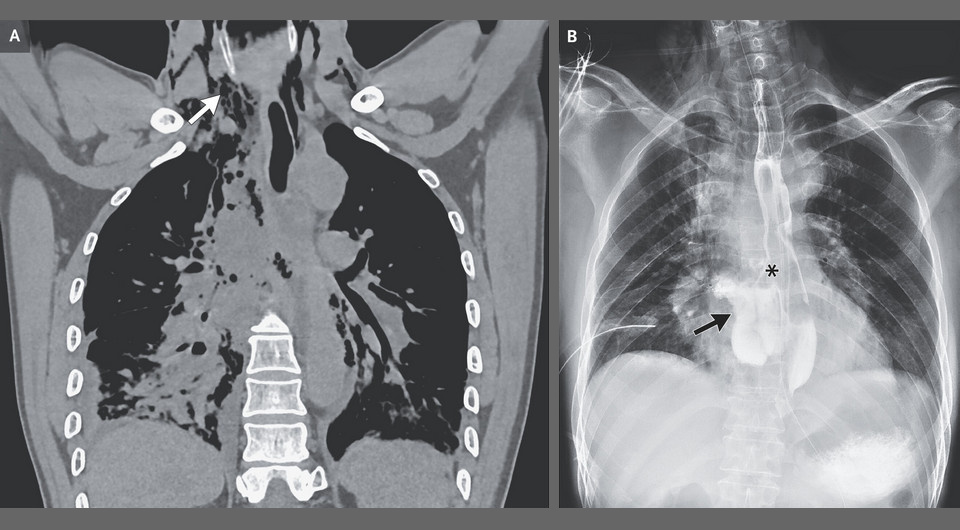

В неотложное отделение китайской больницы поступил 59-летний мужчина с жалобами на сильную боль в грудной клетке в течение пяти часов. За полчаса до появления боли его вырвало большим объемом желудочного содержимого после употребления стритфуда. Ранее значимых жалоб на здоровье у него не было. При осмотре было отмечено частое поверхностное дыхание, при пальпации определялась подкожная крепитация на шее, при аускультации дыхание над основанием правого легкого было ослабленным. На компьютерной томограмме грудной клетки визуализировался воздух в средостении вплоть до шеи, перфорация пищевода, скопление жидкости в правой плевральной полости и ателектаз правого легкого. Пациенту установили плевральный дренаж и получили по нему экссудат без желудочного содержимого, что свидетельствует о реактивном характере плеврита. Эзофагограмма с контрастированием подтвердила обширный разрыв пищевода с проникновением контраста в средостение. Врачи Пэнхуэй Вэй (Penghui Wei) и Вэньюн Чху (Wenyong Zhu) из Больницы Цилу Шаньдунского университета поделились этим случаем в New England Journal of Medicine.

На основании данных обследования мужчине поставили диагноз синдрома Бурхаве — спонтанного разрыва пищевода. В отличие от более распространенного синдрома Мэллори — Вейсса, при котором обычно разрываются слизистая оболочка и подслизистый слой пищевода с последующим кровотечением, синдром Бурхаве характеризуется разрывом всех слоев пищевода и, зачастую, медиастинальной плевры с попаданием туда пищевых масс и без массивного кровотечения. Причиной обоих состояний служит сильная рвота или рвотные позывы. Спонтанный разрыв пищевода без своевременной медицинской помощи угрожает жизни, особенно при попадании желудочного содержимого в средостение и плевральную полость. Пациенту выполнили неотложное торакоскопическое ушивание дефекта пищевода и установили назоеюнальный зонд для искусственного энтерального питания, который оставили при выписке через 35 дней. Визуализация при повторном обследовании через три месяца показала удовлетворительное заживление пищевода, и зонд извлекли.